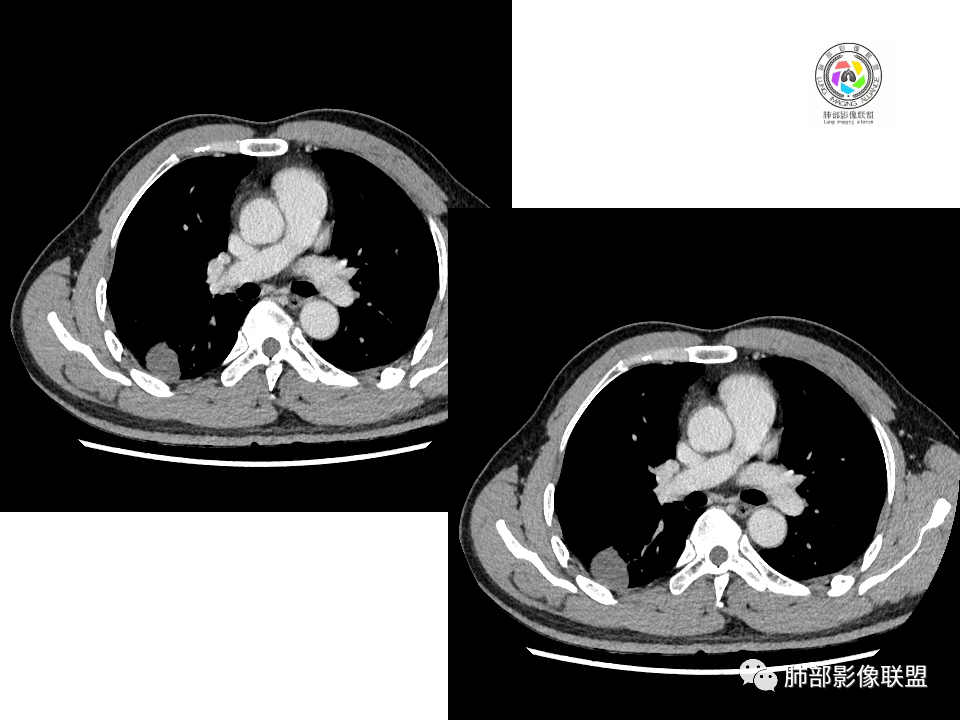

中年男性,体检发现占位。右肺下叶背段胸膜下肿块,周围晕征,有小分叶,与支气管、肺内血管关系不清,形似山丘,重建可见肿块呈D字形凸向肺部。似跨斜裂,似有小凸起与肋下缘相连,增强似有轻微均匀强化。右肺下叶外基底段小结节,位于血管周围,部分边缘平直,轻微均匀强化。考虑二元:一、右下叶背段肿块为肺外病变,神经鞘瘤?SFT?鉴别小细胞癌、隐球菌病;二、右下叶外基底段结节考虑为良性结节、炎性肉芽肿?

大小两个结节,形态类似,强化一致,都是乏血供病变,也无明显坏死,不符合炎性肉芽肿强化特点了,大结节膨隆明显,有局部突出,有长期吸烟史,所以考虑神经内分泌肿瘤可能(小细胞>不典型类癌),另外不典型错构瘤需要鉴别。最终还是需要穿刺病理确定。

②恶性:间叶来源肿瘤,间叶来源的两个病灶的罕见;癌一般还是与支气管关系密切,有如果考虑癌,自然是小细胞癌(山丘征);但是因为没有看到支气管具体情况,不太踏实。

2.右肺下叶背段胸膜下块影,边界清楚光整,上下极见磨玻璃晕,未见明显分叶毛刺和棘状突起,未见胸膜凹陷或胸壁侵入。密度均匀,轻度不均匀强化。未见支气管进入。

4.右肺下叶基底段支气管血管束旁小结节影,边界清楚,强化不明显。注意,这结节在“遥远的”基底段。

1.边缘光整干净,大病灶缺乏坏死等,不符合鳞癌影像学特征。尽管有吸烟史,还是偏年轻。

2.边缘光整,会是小细胞癌或是大细胞癌吗?小细胞癌的肺门纵隔淋巴结增大往往十分夸张,该患者不符合。

注意,基底段支气管血管束旁的小结节影,即便是淋巴结,也与背段病灶引流途径不符。

4.良性占位绕不过去,如发生于该部位的孤立性纤维瘤等……

有老师分析,多发病灶有磨玻璃晕,可以符合隐球菌感染,确实如此。但背段边缘如此锐利的块影还是更容易让人联想到新生物。